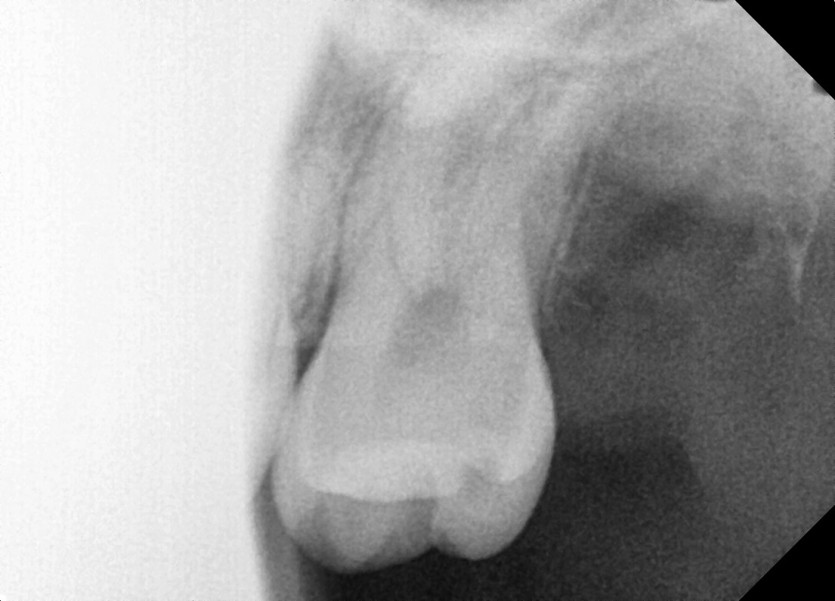

#28,38 사랑니 발치

구강 외과 전문의가 당일 발치하였습니다.